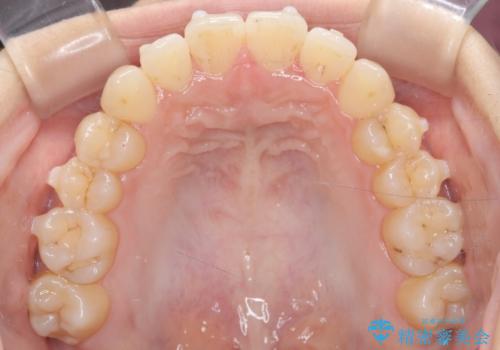

- 前歯のガタガタ(叢生)と、前歯が出ている(突出している)ことを気にされてご来院されました。精密な検査の結果、歯が並ぶスペースと、前歯を引っ込めるスペースの両方が不足していると診断。患者様のご希望に合わせ、透明で目立ちにくいインビザライン(マウスピース矯正)による治療計画を立案しました。スペースの確保は、奥歯全体を奥へ動かす遠心移動と、歯の側面をわずかに削る**IPR(歯間乳頭保護下ストリッピング)**を組み合わせて行い、前歯を効果的に引っ込めることを目指します。

今回の矯正治療では、透明なマウスピース型の装置インビザラインを使用しました。前歯を無理なく引っ込めるスペースを作るため、まず奥歯全体を後方へ移動させる遠心移動を実施。さらに、安全性が確保できる範囲で歯の側面をわずかに削るIPRを併用し、必要なスペースを確保しました。これらの処置により、前歯のデコボコが解消され、前に出ていた前歯も適切に引っ込みました。目立たない装置で治療を完結することで、叢生と突出感が解消され、機能性と審美性が向上した美しい口元を獲得していただけました。